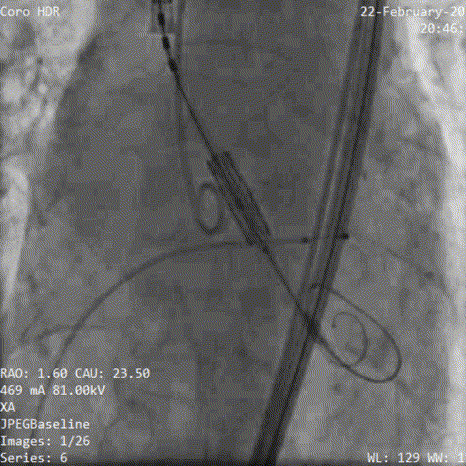

术中影像:

6.造影提示瓣周漏,考虑瓣架形态再次后扩

7.加1cc后扩